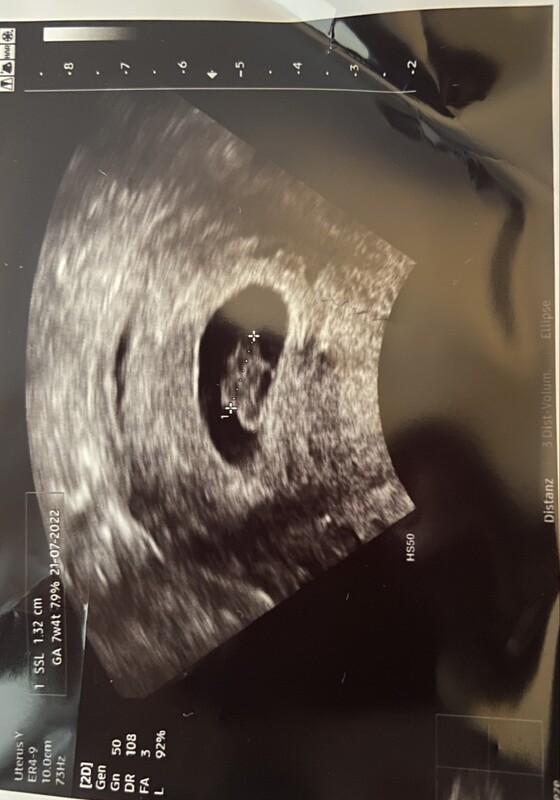

Neunte SSW - Übelkeit & Dauermüde - Tagebücher aus der Schwangerschaft von Sandra aus Stuttgart